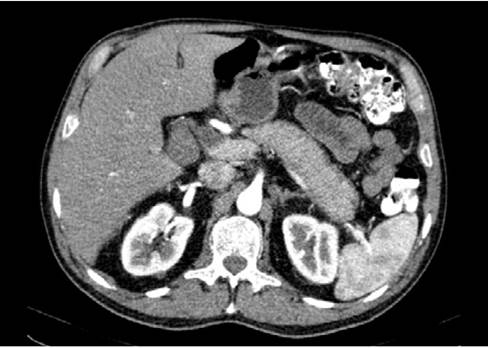

In view of these findings, the patient was admitted to the hospital and during his first day of stay he was assessed by the general surgery department, which considered that he presented hyperbilirubinemia of obstructive pattern with a lesion in the head of the pancreas. So, CT and MRI scans of the abdomen were requested, as well as tests for tumor markers. The test results were available on the following day and reported negative tumor markers (CA 19-9: 14.5 U/mL, alpha-fetoprotein: 2.46 ng/mL, and carcinoembryonic antigen: 2.19 ng/mL). The MRI showed a diffuse alteration in the morphology of the pancreas, with enlargement and obstruction of both the bile duct and the pancreatic duct (without dilatation) (Figure 1). Finally, the CT scan showed an alteration of the peripancreatic fat that formed a low-density "halo" sign and suggested AIP as the main differential diagnosis (Figure 2). Considering these findings, during the third day of hospital stay, the general surgery service considered ruling out an inflammatory process, and in view of a possible autoimmune etiology, requested immunoglobulin blood tests.

Computed axial tomography of the abdomen showing a low- density halo sign around the pancreas due to altered peripancreatic fat.

Figure 2: Computed axial tomography of the abdomen showing a low- density halo sign around the pancreas due to altered peripancreatic fat.

Source: Image obtained while conducting the study.

In the present case, the patient was diagnosed with AIP since both CT and MRI scans showed a diffuse alteration of the pancreatic morphology, an enlargement of the pancreas and an obstruction of the bile duct and pancreatic duct (suggesting narrowing of these organs), with no findings of proximal dilatation, which are characteristic imaging findings of this condition.1,2